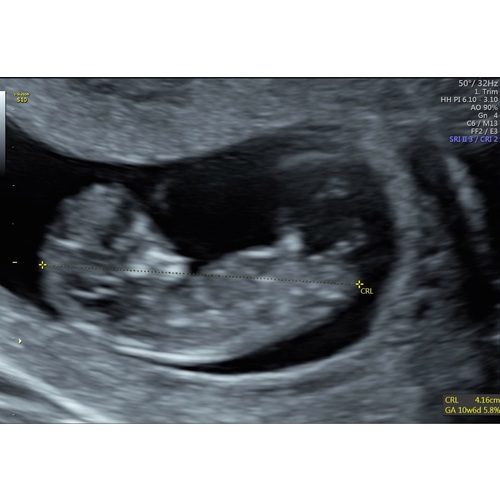

Ik vind het zo spannend wat het geslacht van mijn baby wordt. Ik ben hier zo benieuwd naar. Is er iemand die een gok wilt wagen met de nub theorie. Deze echo is gemaakt met 11 weken. Ik hoor het graag, zelf kom ik er niet uit🥰

Ik zie geen nub, alleen 2 benen 😳

Ik zie zelfs niks nog.

Hierbij nog een foto

Nee sorry, ik zie nog niks..

Is het hierop duidelijker ?

.

Nee het is te vroeg om het te kunnen zien!

Je ziet nub vanaf 12/13 weken wat beter en 14 zie je het al redelijk goed